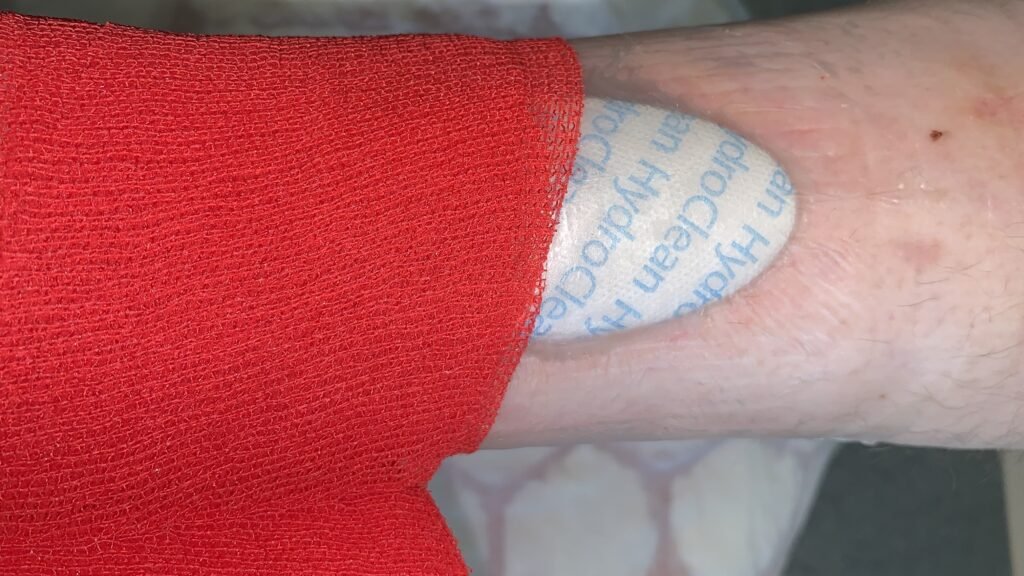

HydroClean

HydroClean cavity

HydroClean Mini